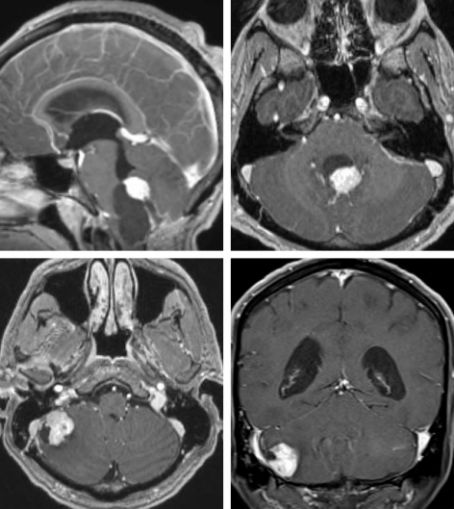

MRI有助于诊断HB,HB瘤体一般表现为囊性,璧上附有结节,壁结节的信号与脑组织的信号相等,增强后有强化,而囊腔内的信号与脑脊液的信号相近。对比增强在诊断HB中起到至关重要的作用,直接影响着下一步治疗计划。

HB的囊腔内含有神经胶质,因此不能显示增强信号,可以根据这点与囊性星形胶质细胞相鉴别,后者的囊壁有环型增强。对HB而言,直接切除增强的瘤体结节即可,而对星形胶质细胞细胞瘤而言,应完整切除增强的囊壁,以获得最佳的疗效。

图1. 上图展示了典型的囊性HB,有一个明显突出的壁结节。下图为小脑半球部位的HB,壁结节实质的比例比囊性部分大。